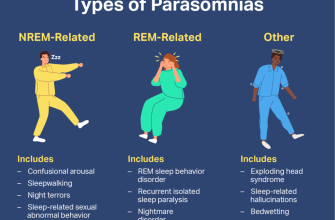

Have you ever experienced sleepwalking? It can be a